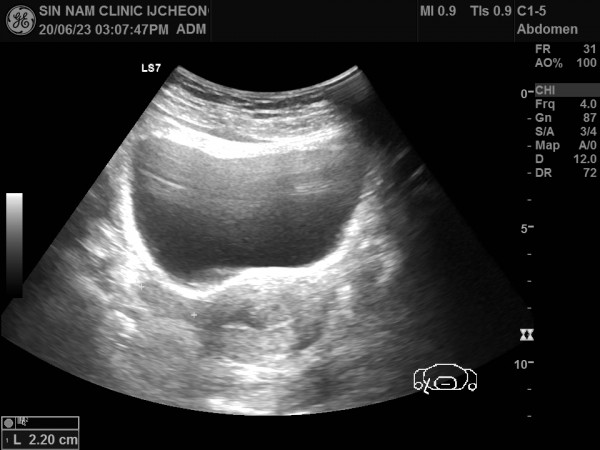

아래 자료는 건강보조식품과 홍삼을 장기 복용한 후 부정출혈이 발생하여 본원에 내원하신 환자분입니다.

내막비후가 지속되어 내막조직검사를 진행하여 내막암 진단을 받으신 분의 초음파 자료입니다.